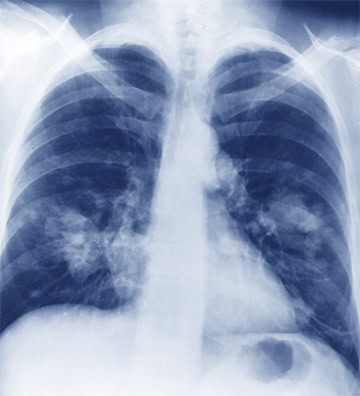

Değişebilir Renk ve Tek Renk Görüntü

ASUS HealthCare ekranlar, farklı derinliklerden röntgen okumaya yardımcı olmak için pozitif ve negatif film moduna sahip renkli ve tek renkli kullanım modları sunar.

Kapalı (Normal, Renk)

Pozitif Film (Tek Renk)

Negatif Film (Tek Renk)